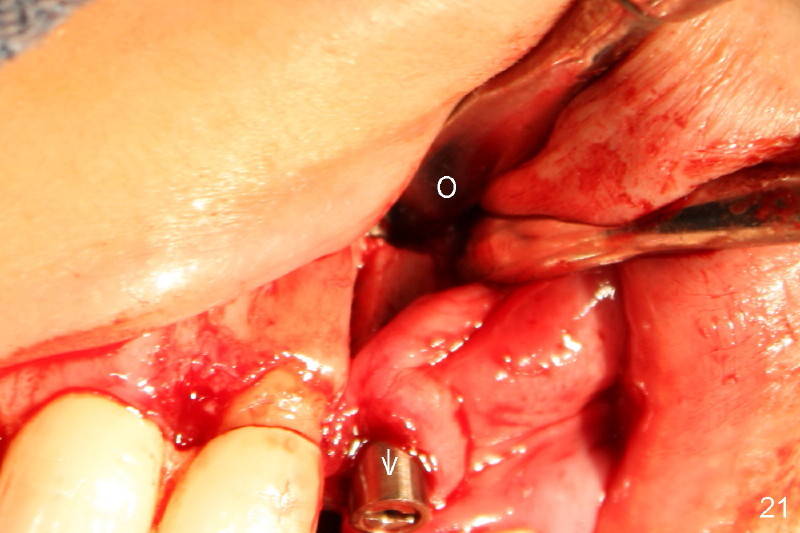

Segmental Osteotomy for Misplaced Implant

This corrective surgery was performed by Dr. Bernee Dunson.

Xin Wei, DDS, PhD, MS 1st edition 12/21/2011, last revision 12/23/2011